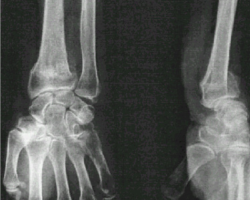

Fracture du poignet